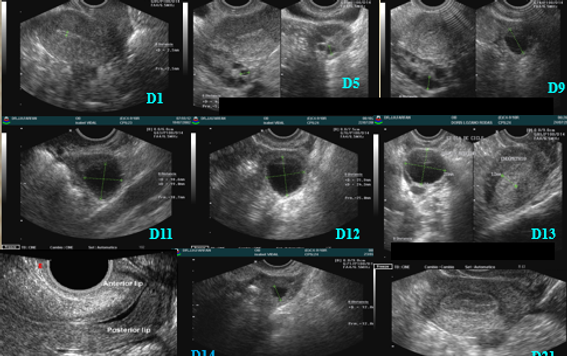

El monitoreo ovulatorio por ecografía permite realizar seguimiento a los cambios del folículo durante el ciclo menstrual, este seguimiento es importante para saber cuando ovula la mujer o diagnosticar las causas de infertilidad, por anomalías en el ciclo menstrual como la ausencia de la ovulación, ausencia de cambios en el endometrio, este examen es realizado por un médico ginecólogo especializado en diagnostico por imágenes, no invasivo y seguro para la mujer.

Este examen consiste en realizar de 4 a 5 ecografías durante el ciclo menstrual de la mujer.